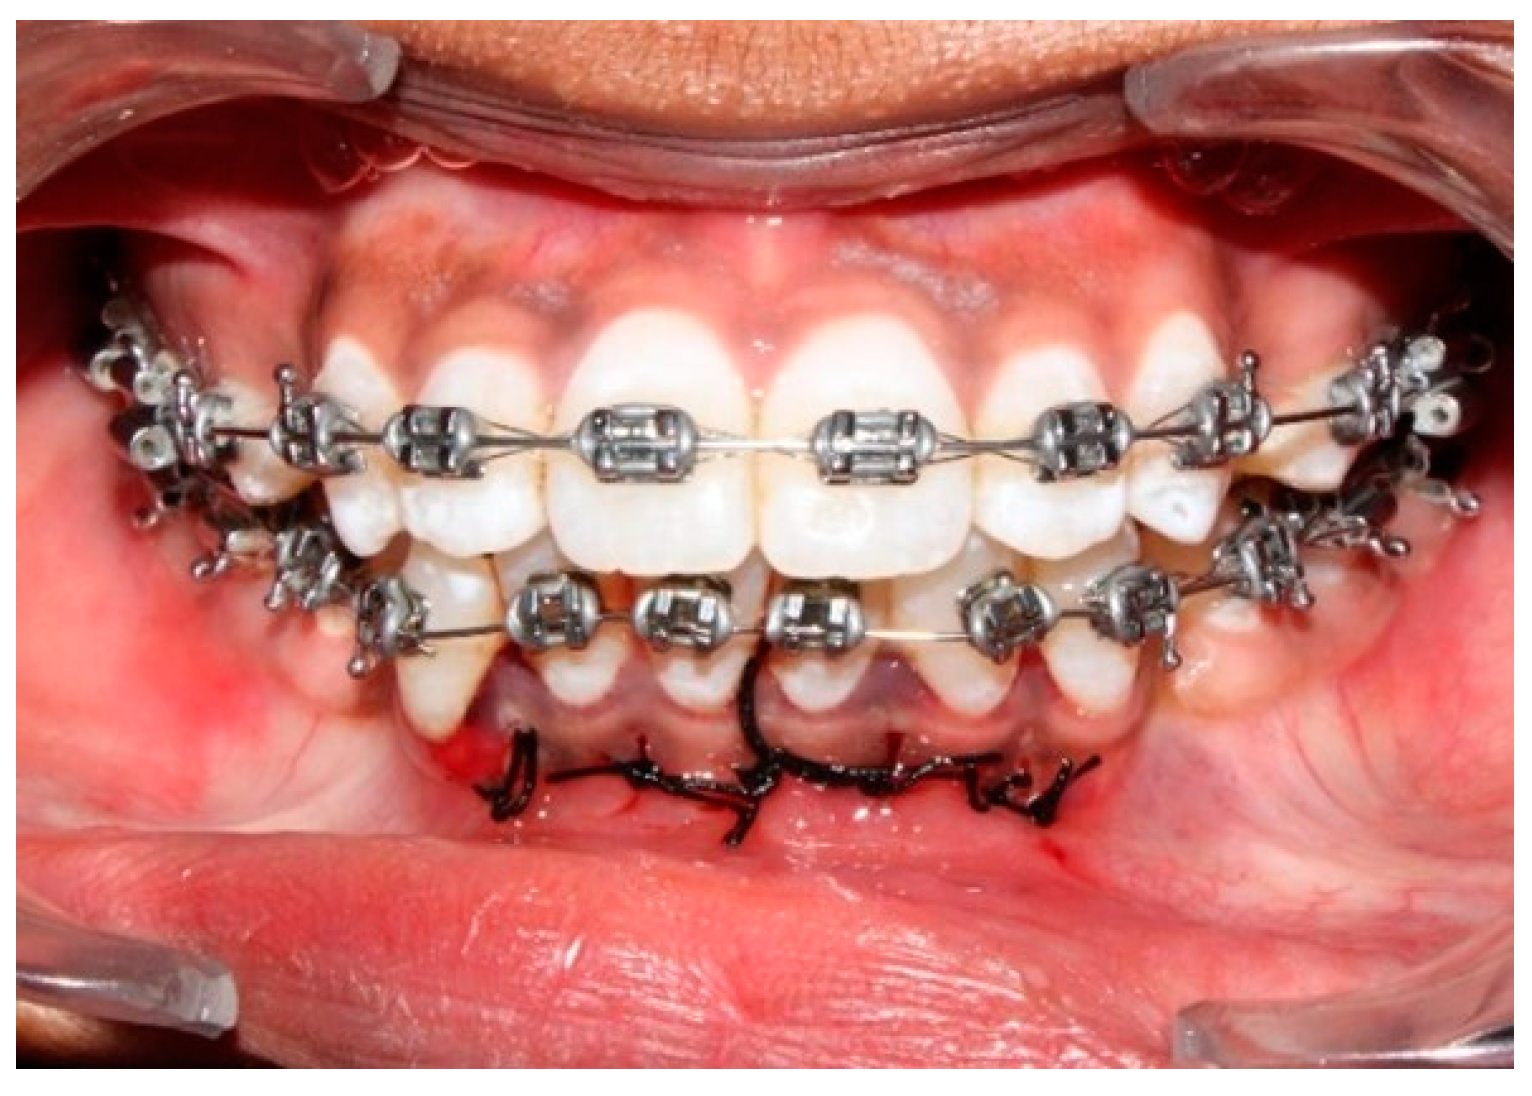

2.3.1. Piezocision Procedure (PZ)

2.4. Orthodontic Procedure